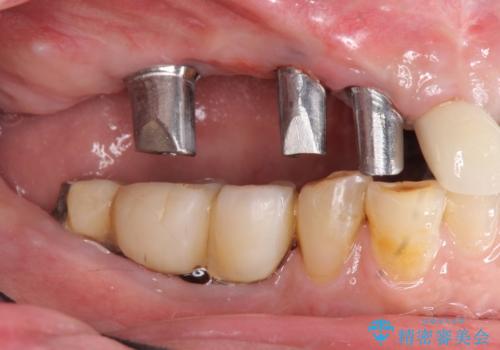

既に埋入されているインプラントは位置が悪いのでそのまま骨内に留置することとし、新たに咬合機能を回復すべく3本のインプラントを埋入すると同時に吸収した骨幅を増やし、安定してインプラントで噛める環境整備を目指します。

インプラントが長持ちするために、インプラント周囲の十分な骨量・角化歯肉の存在・安定した咬合を一つづつ整備する治療を行いました。